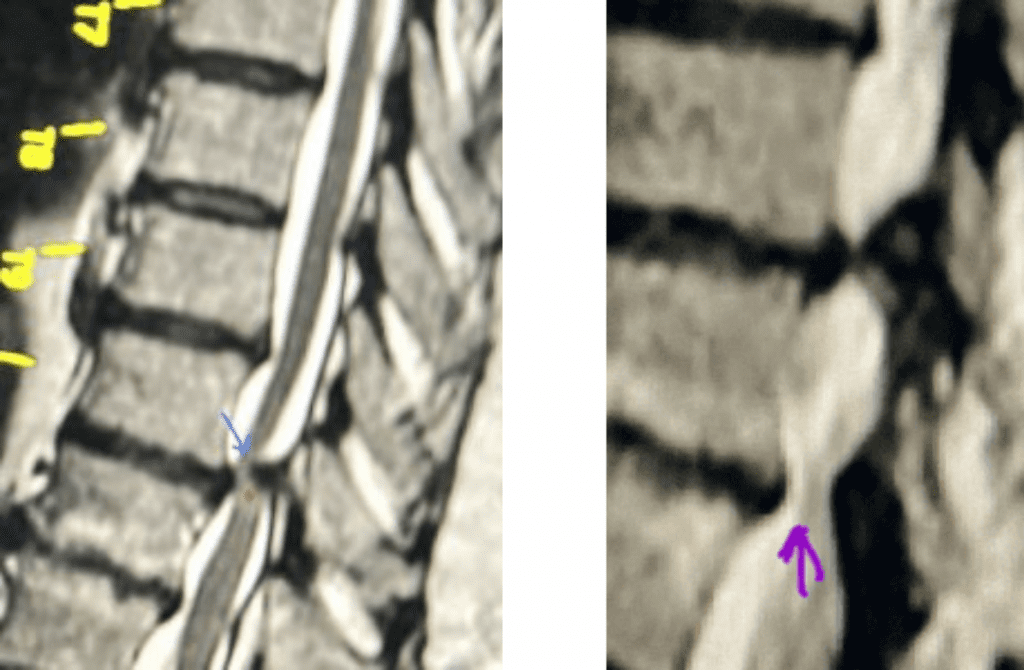

Figure 1. The sagittal MRIs demonstrate a very tight stenosis at T10-11 (blue arrow). Note the area of hyperintensity within the spinal cord at this level representing myelomalacia (red dot). Patient also has significant stenosis at T11-12 (purple arrow).

This 50-year-old morbidly obese female presents with one month of progressive weakness of her lower extremities. She also reported numbness and pain in her thighs. Her right leg was worse, and she had one episode of urinary incontinence. She had some back pain. She was ⅖ strength in her right hip flexor and quadriceps. She was ⅘ in her left lower extremity. MRI (Figure 1 and Figure 2) revealed very tight stenosis circumferentially at T10-11 secondary to facet hypertrophy and anterior disc osteophyte complex with associated myelomalacia of the spinal cord. There was also stenosis to a lesser degree but still significant at the T11-12 level.

Figure 2. Axial images comparing a normal appearing spinal cord with a white fluid ring around it versus an axial image of the T10-11 level demonstrating circumferential stenosis.